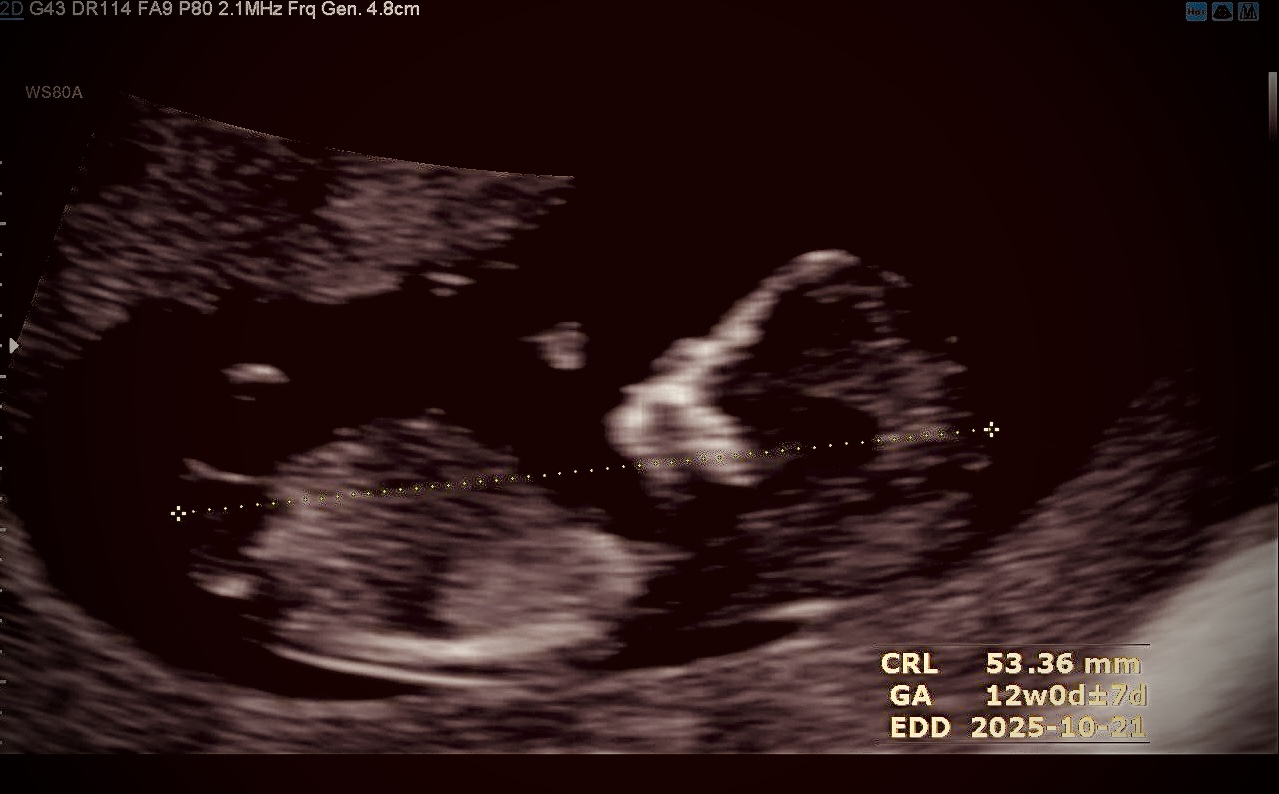

عکس جنینم

دوستان گلم مادران باتجربه عزیزان من رفتم آن تی ولی دکتر نگفت جنسیت صدرصدی چیه فقط گفت شاید دختر باشه ولی از نظر من و اطرافیان خیلیا میگن به خاطر جمجش و پایین تنش که یچی کوچیک داره پسره من عکسشو میزارم لطفا نظر بدین

هوش مصنوعی گف ۱۲ هفتس انگار و خیلی دقیق نمیشع گف ولی احتمال پسر داددیگه نمیدونم درست دربیاد یا نه

مال منم ۱۲ هفته و چهار روز بود دیروز که سونو دادم. زائده ای نیست من از کل سونوگرافی فیلم گرفتم اون پا هست هوش مصنوعی گفت با توجه به زاویه nub که بیشتر از سی یا کمتر از سی باشه میشه حدس زد و دقیق نمیشه گفت